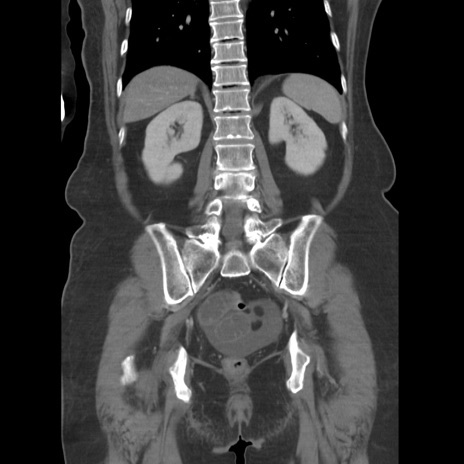

症例19(冠状断像)

【症例】80歳代女性

【主訴】下腹部痛

【現病歴】約8時間前より下腹部痛の出現あり、救急外来受診。

【既往歴】両側付属器切除

【身体所見】意識清明、下腹部正中に手術痕あり、その部位に一致して圧痛と反跳痛あり。腸蠕動音は亢進。

【データ】WBC 9300、CRP 0.15